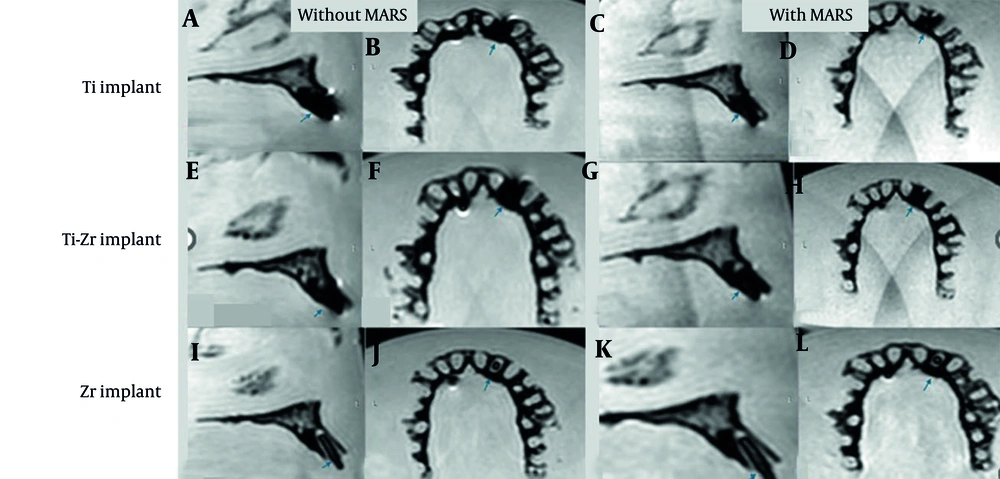

Volumes, calculated in cubic millimeters using the software’s “Statistics” tab, were reported separately for signal loss and pile-up artifacts. For signal loss, the implant volume was subtracted from the total segmented volume (15), while pile-up volumes were directly obtained from the segmented regions. Manual delineation of affected areas was performed slice by slice to maximize precision. Examples from the T2W sequence are shown in Figures 5. and 6.

T2-weighted (T2W) magnetic resonance imaging (MRI) images for titanium (Ti), titanium-zirconium (Ti-Zr), and zirconia (Zr) implants in the anterior maxillary region, without (A, B, E, F, I, and J) and with (C, D, G, H, K, and L) metal artifact reduction sequences (MARS) technique (Blue arrows denote to implant site).

T2-weighted (T2W) magnetic resonance imaging (MRI) images for titanium (Ti), titanium-zirconium (Ti-Zr), and zirconia (Zr) implants in the posterior maxillary region, without (A, B, E, F, I, and J) and with (C, D, G, H, K, and L) metal artifact reduction sequences (MARS) technique (Blue arrows denote to implant site).